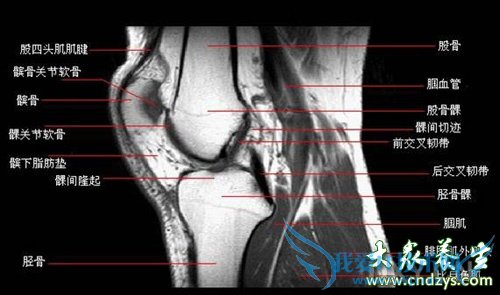

Å®ÐÔÓëÄÐÈËÏà±È£¬¸üÈÝÒ×À­ÉËÏ¥¡¢õ׵ȹؽڵÄÈÍ´ø¡£ÒòΪ£¬Å®ÐÔ÷Ų¿¿í´ó£¬Ê¹µÃÈÍ´ø³ÐÊÜ×÷ÓÃÁ¦¹ý´ó£¬Òò´ËÅ®ÐÔµÄÈÍ´ø£¬ÌìÉú¾Í±ÈÄÐÈË´àÈõµÃ¶à¡£Æä´Î£¬Å®ÐÔµÄÔ˶¯·´Ó¦Ò»°ã±ÈÄÐÐÔÂý£¬³öÏÖΣÏÕʱ£¬²»Äܼ°Ê±»º½â£¬Ò²¾Í¸üÈÝÒ×ÊÜÉË¡£